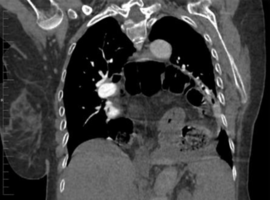

The Unexpected Squeeze: When a Hiatus Hernia Induces Cardiac Tamponade and Causes a Myocardial Infarction

Volume 5, Issue 4

: